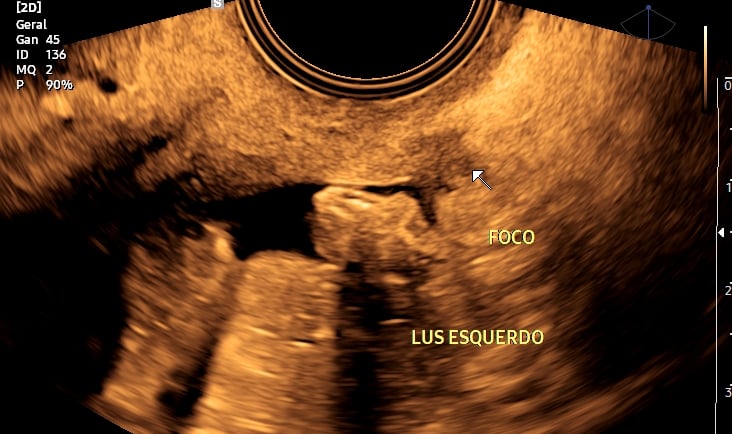

Foco de endometriose em ligamento ulterossacro esquerdo em paciente com queixas de cólicas e dores pélvicas.

4. Ultrassonografia para Diagnóstico de Endometriose

A endometriose é uma condição comum que pode causar dor pélvica e infertilidade. O ultrassom especializado, principalmente o transvaginal com preparo intestinal, pode detectar implantes endometrióticos profundos e orientar o tratamento.